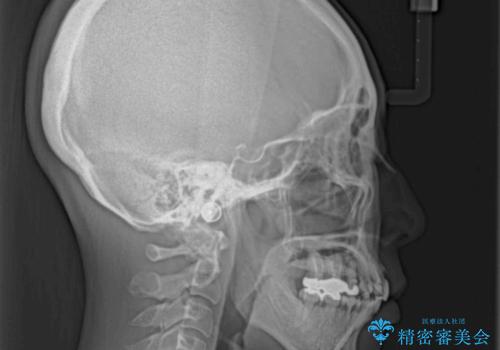

口元を引っ込めることができたため、口を閉じるときに力が入っていて皺のよっていた顎先も、スムーズに閉じられるようになったことで力がかからなくなりました。

変色して気になっていた前歯も、オールセラミッククラウンで自然な色合いにすることができました。